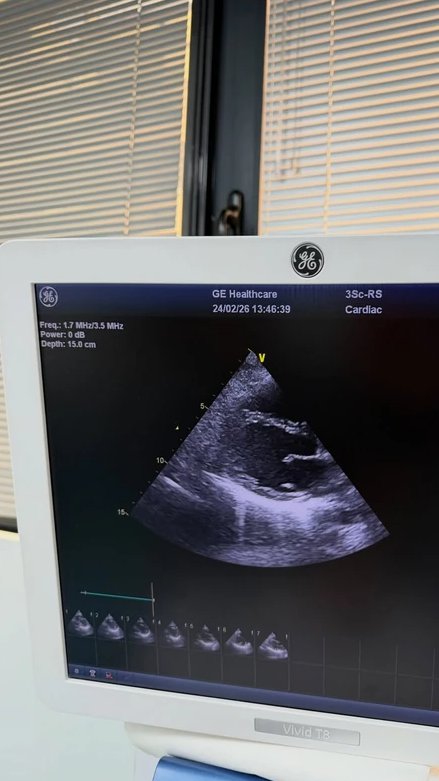

Didi je istakla da je sve počelo sa vrtoglavicom i da nedeljama nije znala šta se dešava. Sada je priključena na uređaj - holter, koji kontinuirano prati rad srca ili krvni pritisak tokom dužeg vremenskog perioda.

- Sve je počelo sa vrtoglavicom i kratkim dahom. Nedeljama nisam znala šta se dešava, a lekari su isprva mislili da je u pitanju samo obična prehlada. Kasnije sam saznala da je virus uticao na moje srce, izazvavši subakutni perikarditis, i da je moj autonomni nervni sistem napalo nekoliko virusa odjednom, što mi je prouzrokovalo POTS (posturalni ortostatski tahikardni sindrom). Želela sam da podelim ovo sa vama kako bi moji obožavaoci razumeli zašto me nije bilo. Nadam se da ću se ubrzo oporaviti i vratiti karijeri koju najviše volim - napisala je Dijana.